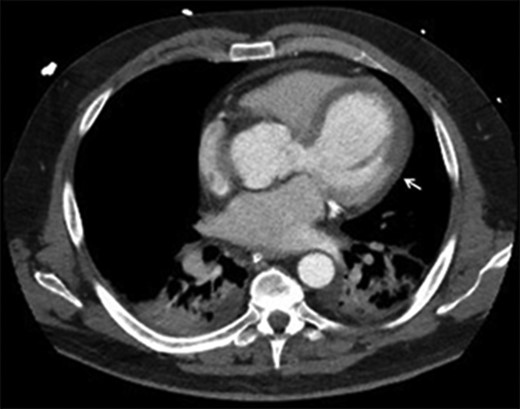

The patient is a 53-year-old man with a history of hypertension. He sustained an out of hospital cardiac arrest secondary to an anterolateral ST elevation myocardial infarction (STEMI). He was loaded with Prasugrel and heparin and was treated with drug eluting stents in the LM, proximal left anterior descending (LAD) and left circumflex coronary arteries. Because of persistent cardiogenic shock, an intra-aortic balloon pump was placed. Transthoracic echocardiogram (TTE) revealed severe left ventricular (LV) dysfunction with an ejection fraction of 25%, moderately severe aortic regurgitation, aortic root dissection and he was subsequently transferred to our institution. Upon arrival, he was mechanically ventilated and required increasing doses of inotropes. He experienced frequent supraventricular and ventricular arrhythmias. CT scan of the thoracic aorta revealed a dilated aortic root (maximum transverse diameter of 5 cm) and a dissection flap involving the non-coronary and left coronary sinuses with concern of transmural hypoperfusion of LAD territory (Fig. 1).

CT aorta: arrow points at the differential myocardial enhancement corresponding to large area of infarct.